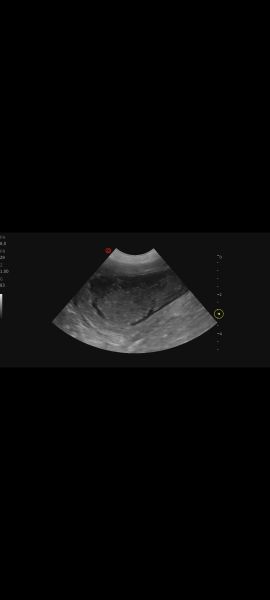

Hi, my vet performed an ultrasound on 7 year old lab mix because of an UTI .She said her bladder walls look thickened and spongy. She's concerned. Can you tell anything? I'll try to add more pics under commentsScreenshot_20251230_161511_PhotosScreenshot_20251230_161500_PhotosScreenshot_20251230_161447_Photos